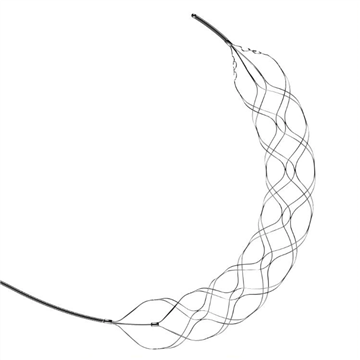

Trombektomija Stent RetrieverStent retriveri su endovaskularni uređaji koji mogu ukloniti ugruške iz velikih arterija kod pacijenata s akutnim ishemijskim moždanim udarom. Ovi uređaji su dizajnirani za isporuku kroz kateter u art

Šta je trombektomija stent retrivera?Stent retriver trombektomija je minimalno invazivna hirurška procedura koja se koristi u liječenju ishemijskog moždanog udara. To je oblik neurovaskularne intervencije koja uključuje korištenje stent

Intrakranijalni stent retriverNa tržištu je otkriven uređaj za vraćanje ugrušaka koji se može koristiti u intrakranijalnim krvnim žilama, a koji uključuje kostur koji se može uplesti od žica od legure sa memorijom oblika kako bi s